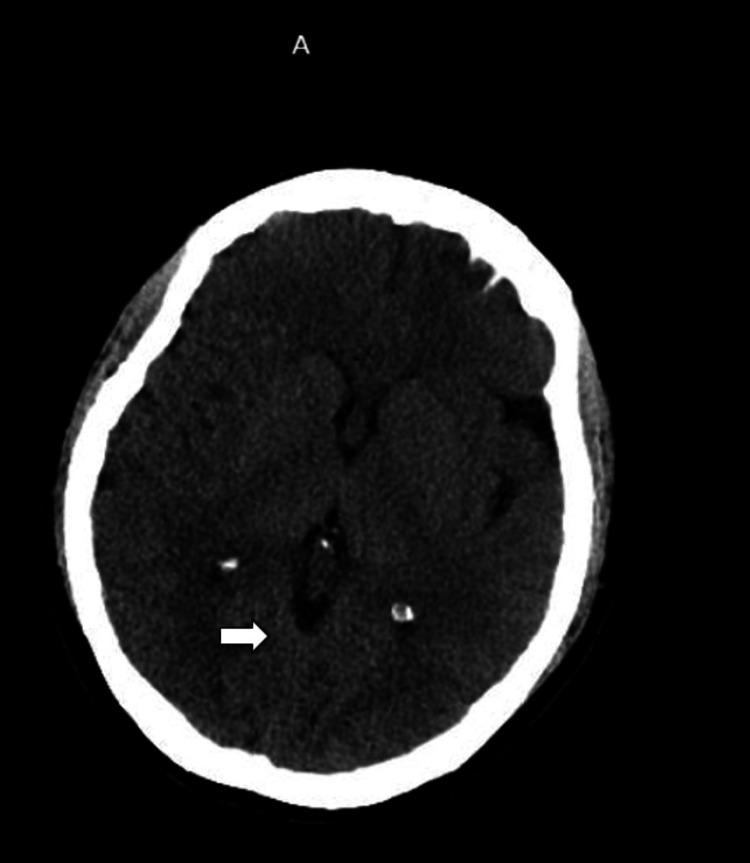

Pneumocephalus is a rare but potentially serious complication of spinal procedures, characterized by the presence of intracranial air. This report presents the case of a 40-year-old female who developed pneumocephalus following a lumbar epidural steroid injection. She presented to the emergency department with a persistent headache, blurred vision, and eye pain, which began shortly after the procedure. Computed tomography (CT) scans of the head and lumbar spine revealed several air pockets in the cerebellar cisterns and the left frontal horn, as well as in the epidural and paraspinal regions. Despite the presence of intracranial air, the patient's symptoms gradually improved with conservative management, including bed rest, caffeinated drinks, intravenous fluids, and symptomatic relief with butalbital-acetaminophen-caffeine. A repeat CT scan on day four showed a reduction in air pockets, and by day 10, all air pockets had resolved without the need for neurosurgical intervention. The patient's headaches subsided, though she experienced mild residual vision changes. This case emphasizes the importance of recognizing pneumocephalus as a potential complication of epidural steroid injections and highlights the efficacy of conservative treatment. While most cases of simple pneumocephalus resolve spontaneously, careful monitoring is essential to prevent progression to tension pneumocephalus, a life-threatening condition that requires urgent surgical intervention. Further studies are needed to evaluate the risks and outcomes of different techniques used during epidural procedures.

气颅是脊柱手术中一种罕见但可能严重的并发症,其特征为颅内存在气体。本报告介绍了一名40岁女性在接受腰椎硬膜外类固醇注射后发生气颅的病例。她在手术后不久因持续头痛、视力模糊和眼痛就诊于急诊科。头部和腰椎的计算机断层扫描(CT)显示小脑脑池和左额叶角以及硬膜外和椎旁区域有多个气腔。尽管存在颅内气体,但通过保守治疗,包括卧床休息、饮用含咖啡因饮料、静脉输液以及使用布他比妥-对乙酰氨基酚-咖啡因缓解症状,患者的症状逐渐改善。第四天的重复CT扫描显示气腔减少,到第十天时,所有气腔均已消失,无需神经外科干预。患者的头痛症状消退,不过仍有轻度视力残留改变。该病例强调了认识到气颅是硬膜外类固醇注射潜在并发症的重要性,并突出了保守治疗的有效性。虽然大多数单纯性气颅病例可自行缓解,但仔细监测对于预防进展为张力性气颅至关重要,张力性气颅是一种危及生命的情况,需要紧急手术干预。需要进一步研究来评估硬膜外手术中使用的不同技术的风险和结果。